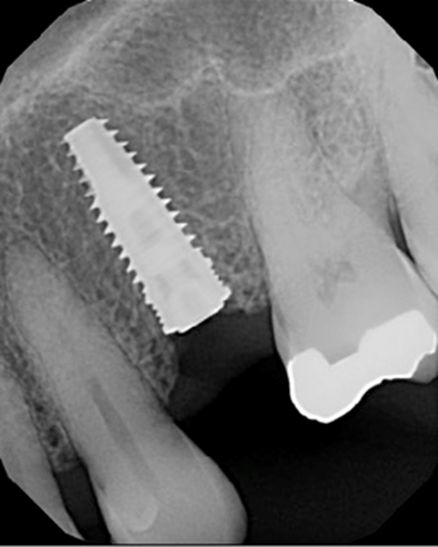

Resident Case Photos

The following are before and after photos of dental patients who have been treated by the residents at NYC Health + Hospitals/South Brooklyn Health. To apply to the program visit the Dental GPR Page and click on Application Information.

Implant Restoration